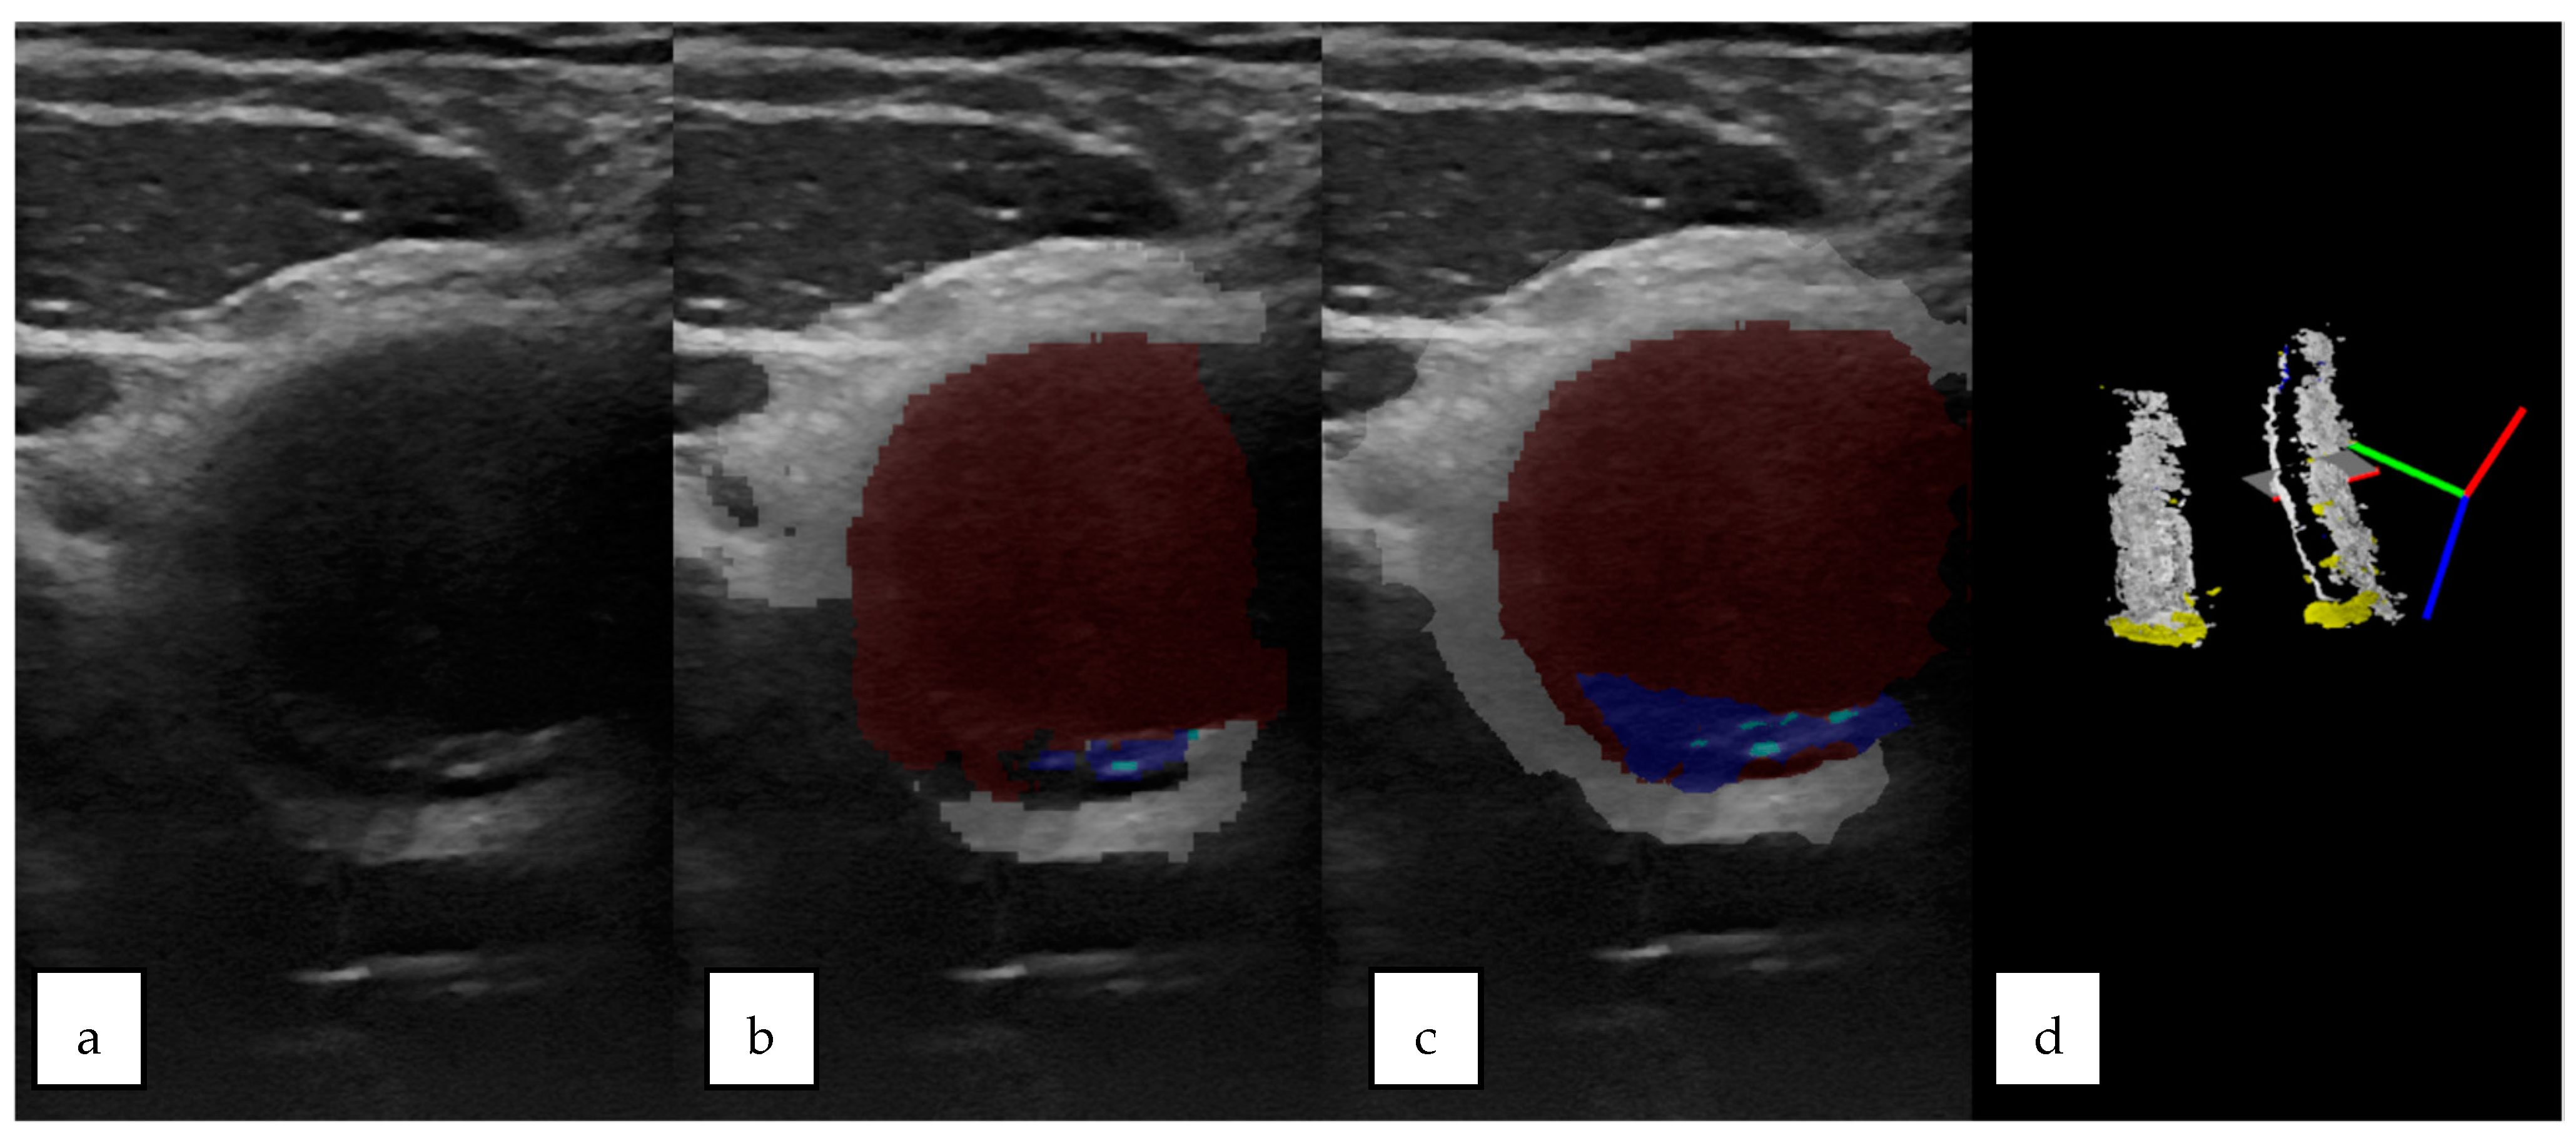

2.7. 3D Ultrasound Reconstructions of the Carotid Arteries

2.8. Qualitative Analysis of the 3D US Reconstructions

3.2. 3D US Reconstruction Compared with CT Angiography